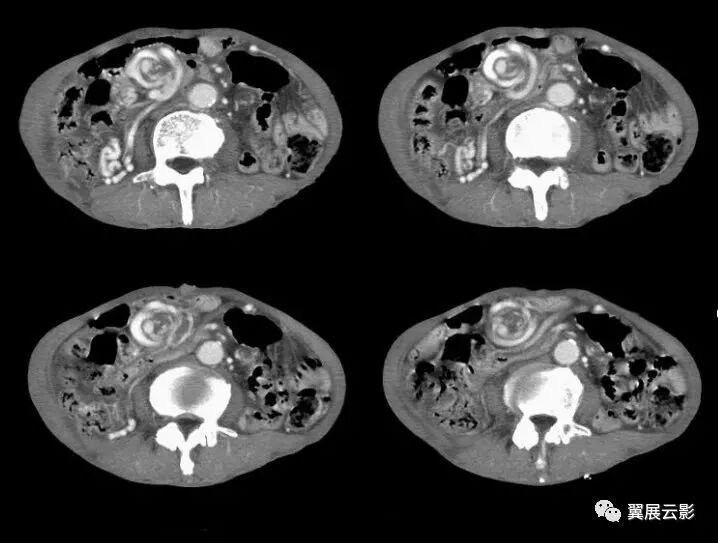

下图是闭襻性的肠梗阻

闭袢型肠梗阻

图1,2 肠系膜脂膜炎。

图1 为 MSCT平扫,显示肠系膜密度增高,CT值为 – 47 HU,与腹腔正常脂肪有清楚分界 (箭头) ,且显示肠系膜血管(箭)周围无受累,呈“脂肪环征”。

图2 为MSCT门静脉期,显示肠系膜无明显强化,CT值为 – 45 HU,与腹腔脂肪有清楚界限,形成假包膜征 (箭头) ,邻近肠管有推移改变。

17、脂肪环征

肠系膜脂膜炎的CT表现。肠系膜脂肪组织密度增高(-40–60H。),呈边界清楚、密度不均匀的单个或多个软组织密度肿块,肿块围绕系膜大血管但不累及血管,肠系膜血管周围可有脂肪存在,形成脂肪环征。

肠系膜脂膜炎以慢性毙比细胞浸润,脂肪坏死和纤维组织形成“假肿瘤结节”为特征,包绕但不侵犯肠系膜血管,肠系膜曲静脉血管位于病变内,邻近血管脂肪密度正常,形成脂肪环征。

CT是诊断肠系膜脂膜炎的有效方法。典型CT表现为与腹膜后脂肪密度相比肠系膜脂肪组织密度增高(-40~-60Hu).呈边界清楚、密度不均匀的单个或多个软组织密度肿块,其内可见脂肪密度和低密度囊变区。肿块围绕系膜大血管但不累及血管,肠襻向四周移位。部分表现为肠系膜根部围绕肠系膜血管以脂肪成分为主的肿块,内有散存放射状、条索样、结节样软组织密度区。有时表现为有包膜的密度不均匀肿块,内有脂肪、水样或软组织密度区。少数表现为多房囊性肿块(由于淋巴管和血管阻塞引起的淋巴管扩张)。

① 脂肪环征,肠系膜血管周围可有脂肪存在,形成脂肪环征,其出现率为85%~88.8%;

② 假包膜征,肿块周阿有条带状软组织密度影环绕,病理上为纤维组织,其厚度一般为3mm,小超过iOmm,出现率为50%–66.6%,

③ 软组织结节,为肠系膜淋巴结散在分布于肿块中,多数<5mm,80%的患者有此征象;

④ 增强前后无明显密度改变,而其内肿大淋巴结可出现增强,可能与淋巴结的炎性改变有关。